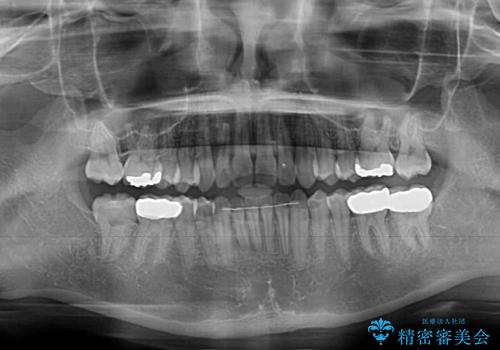

矯正治療後は、奥歯の虫歯や銀歯を補綴・修復治療することとしました。

上顎歯列を下顎に対して4mmほど移動させる必要があったため、治療は長期化することが予想されましたが、患者様にはこちらの期待以上にゴムかけなどに協力いただき、補綴治療も含めて2年強で終えることができました。